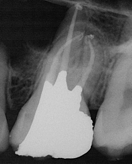

Conventional Treatment with Standard Core Restoration

Conventional endodontic treatment with alloy core build up